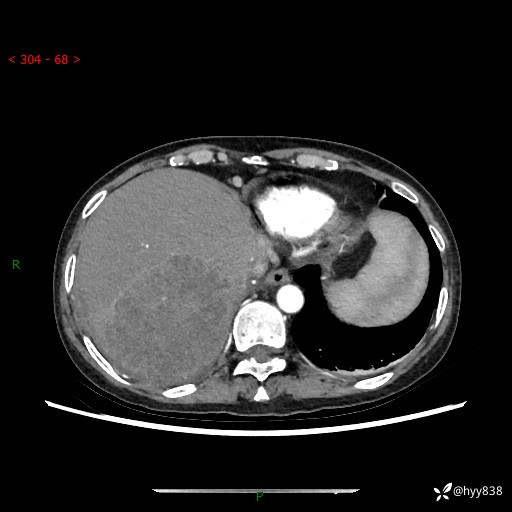

上腹部CT平扫